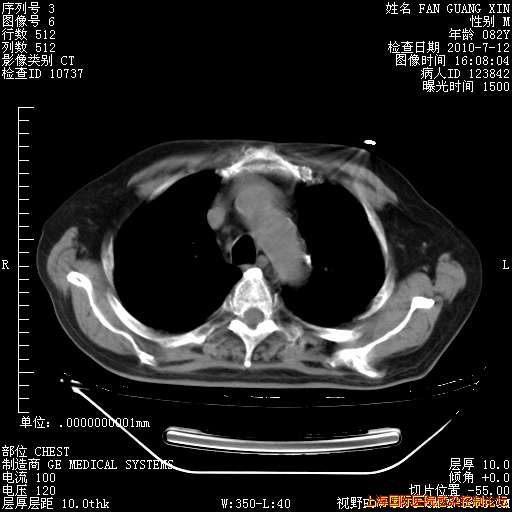

今天复查CT